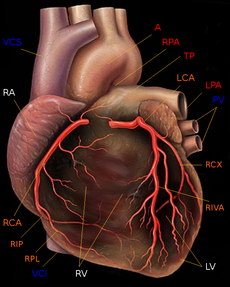

In the human body, the heart is usually situated in the middle of the thorax with the largest part of the heart slightly offset to the left (although sometimes it is on the right, see dextrocardia), underneath the breastbone (see diagrams). The heart is usually felt to be on the left side because the left heart (left ventricle) is stronger (it pumps to all body parts). The left lung is smaller than the right lung because the heart occupies more of the left hemithorax. The heart is enclosed by a sac known as the pericardium and is surrounded by the lungs. The pericardium comprises two parts: the fibrous pericardium, made of dense fibrous connective tissue; and a double membrane structure containing a serous fluid to reduce friction during heart contractions (the serous pericardium). The mediastinum, a subdivision of the thoracic cavity, is the name of the heart cavity.

The apex is the blunt point situated in an inferior (pointing down and left) direction. A stethoscope can be placed directly over the apex so that the beats can be counted. It is located posterior to the 5th intercostal space in the left mid-clavicular line. In normal adults, the mass of the heart is 250-350 g (9-12 oz), or about three quarters the size of a clenched fist, but extremely diseased hearts can be up to 1000 g (2 lb) in mass due to hypertrophy. It consists of four chambers, the two upper atria (singular: atrium ) and the two lower ventricles.

In humans, the function of the right side of the heart (see right heart) is to collect de-oxygenated blood, in the right atrium, from the body and pump it, via the right ventricle, into the lungs ( pulmonary circulation) so that carbon dioxide can be dropped off and oxygen picked up ( gas exchange). This happens through the passive process of diffusion. The left side (see left heart) collects oxygenated blood from the lungs into the left atrium. From the left atrium the blood moves to the left ventricle which pumps it out to the body. On both sides, the lower ventricles are thicker and stronger than the upper atria. The muscle wall surrounding the left ventricle is thicker than the wall surrounding the right ventricle due to the higher force needed to pump the blood through the systemic circulation.

Starting in the right atrium, the blood flows through the tricuspid valve to the right ventricle. Here it is pumped out the pulmonary semilunar valve and travels through the pulmonary artery to the lungs. From there, blood flows back through the pulmonary vein to the left atrium. It then travels through the mitral valve to the left ventricle, from where it is pumped through the aortic semilunar valve to the aorta. The aorta forks, and the blood is divided between major arteries which supply the upper and lower body. The blood travels in the arteries to the smaller arterioles, then finally to the tiny capillaries which feed each cell. The (relatively) deoxygenated blood then travels to the venules, which coalesce into veins, then to the inferior and superior venae cavae and finally back to the right atrium where the process began.